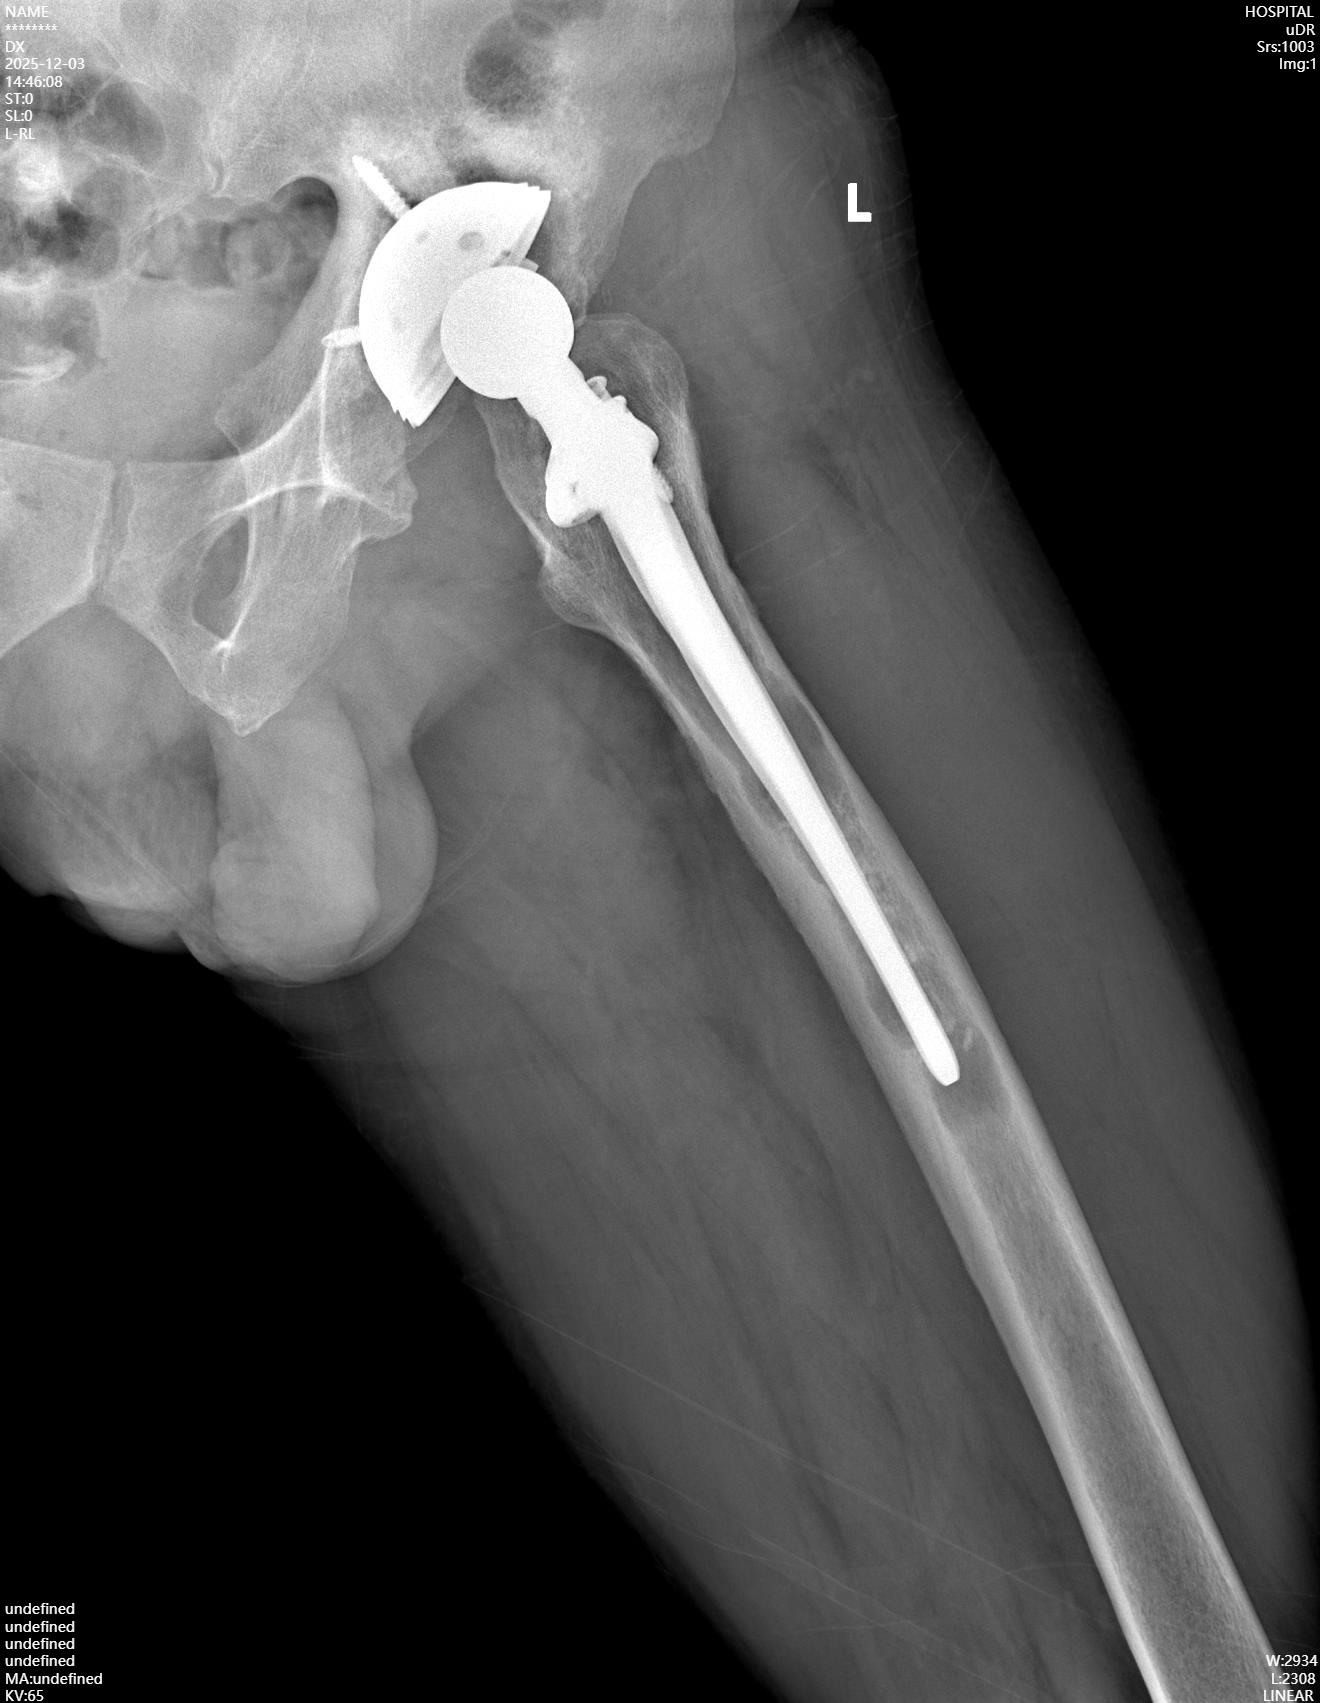

病例資料:患者男,51歲,男性,因“左髖關節(jié)置換術后20年,酸脹不適1年余”入院?;颊?0余年前因股骨頭壞死后行左髖關節(jié)置換手術,術后恢復良好,可恢復日常勞動及一般運動,愛好登山活動,無明顯外傷史。1年余前開始出現(xiàn)左髖部酸脹不適,下肢不敢發(fā)力,并且逐漸出現(xiàn)跛行。入院查體:雙下肢不等長,骨盆向患側傾斜,髖部無明顯腫脹,腹股溝區(qū)壓痛,患側髖關節(jié)過屈時,疼痛稍加重,患側4字征試驗(+),患側滾原木測試(-),患側髖關節(jié)屈伸活動無明顯受限,患側下肢肢端感覺血運未見明顯異常。

入院X線檢查提示:左髖關節(jié)假體松動,髖臼假體及旋轉中心上移,假體周圍可見明顯的透亮線。入院診斷:左側人工髖關節(jié)置換術后假體松動。入院后在髖關節(jié)超聲引導下進行左髖關節(jié)穿刺,穿刺液體進行常規(guī)檢查未見感染征象,血沉及CRP正常,因此屬于無菌性假體松動。

完善術前準備后,擇期行左側人工髖關節(jié)翻修術,術中發(fā)現(xiàn)左側髖臼假體上移,原有的髖臼中心已被疤痕組織填充,取出髖臼周圍出現(xiàn)深灰色的金屬細微顆粒,取出髖臼假體后出現(xiàn)髖臼頂部骨質缺損。股骨側假體也出現(xiàn)松動,股骨柄遠端未見明顯骨長入。

取出假體后,在髖臼頂部缺損處采用金屬墊塊填充后可穩(wěn)固安裝髖臼臼杯,完美恢復髖臼的旋轉中心;股骨側采用組配式假體、遠端早期獲得穩(wěn)定。術中仔細進行止血處理,修復周圍切開的軟組織,術中充分止血后不放置引流管。術后第一天扶雙側拐杖下地行走,恢復良好。